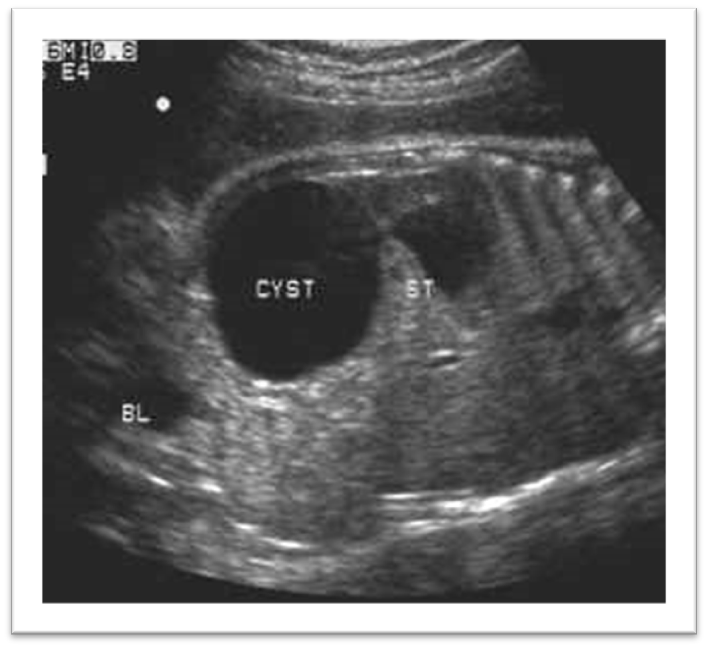

What is this image showing?

Ovarian cyst